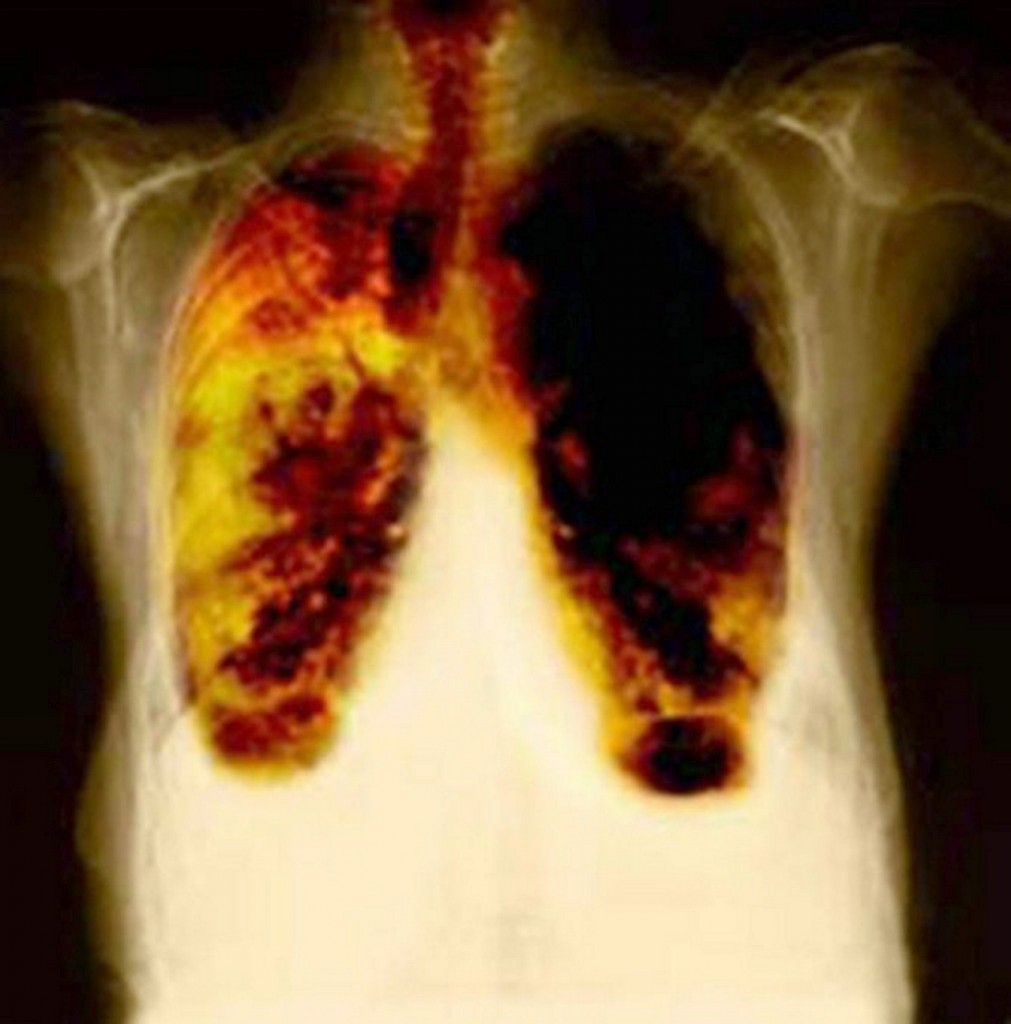

¿Cómo afecta a nuestro organismo a través del ejercicio? Estando en exposición, con el simple hecho de inhalar, las partículas de aire contaminado entran en nuestro sistema respiratorio y cardiovascular, disminuyendo el oxígeno y dañando gradualmente los pulmones.

Una persona, cuando realiza una actividad física, aumenta en un 20% el consumo de aire, por lo que se multiplica el riesgo de padecer cansancio, irritación, tos y sensación de ahogo. A largo plazo, la exposición constante bajo estas condiciones, provoca enfermedades respiratorias como asma, bronquitis, edema pulmonar, cáncer y un paro respiratorio, que llevaría a la muerte.